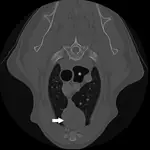

The following day, thoracic CT was performed to better evaluate the mass, determine the size of regional lymph nodes, and look for evidence of pulmonary metastasis. A well circumscribed, partially cystic mass was identified in the cranial mediastinum (Figure 2). There was no evidence of thoracic lymphadenopathy or pulmonary metastases. An ultrasound-guided, fine-needle aspirate of the mass was obtained; cytologic diagnosis was consistent with probable lymphocyte-predominant thymoma with mononuclear cell inflammation and hemorrhage.

Figure 2. Thoracic CT showing a circumscribed, cystic, round mass in the cranial mediastinum (arrow). Dilation of the gas-filled esophagus is also visible (*).